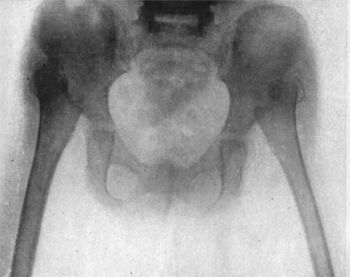

55.Multiple Fracture of Pelvis through Horizontal and Descending Rami of both Pubes, and Longitudinal Fracture of left side of Sacrum123

56.Fracture of Left Iliac Bone; and of both Pubic Arches124

57.Many-tailed Bandage and Binder for Fracture of Pelvic Girdle125